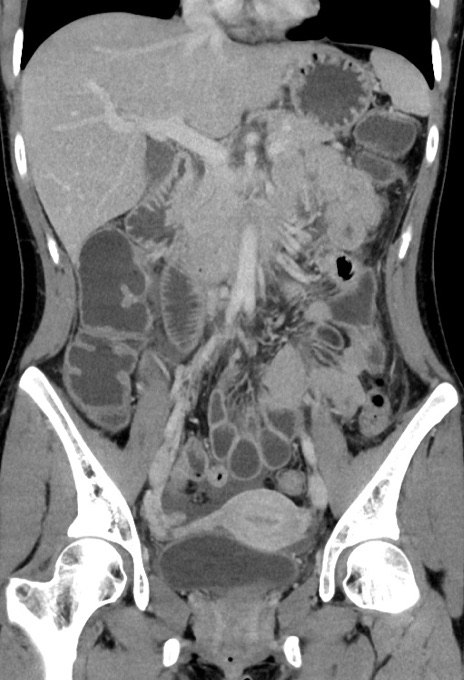

症例17(冠状断像)

【症例】20歳代女性

【主訴】嘔吐、下腹部痛

【現病歴】昨日夕食後に嘔吐し下腹部痛が出現。本日になっても嘔吐持続し改善しないため来院。

【身体所見】意識清明、BT 37.2℃、BP 108/67mmHg、腹部:平坦、やや硬、下腹部正中から右にかけて圧痛あり、反跳痛軽度あり、tapping pain(+)。

【データ】WBC 13600、CRP 14.94